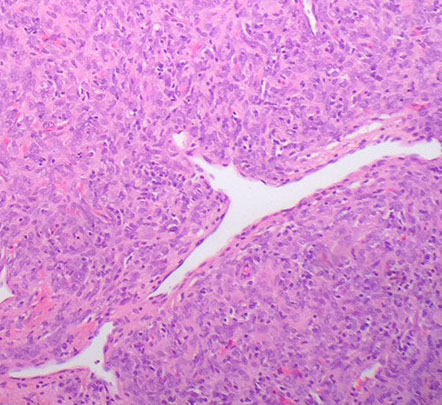

Dysplastic Gangliocytoma of the Cerebellum

- aka Lhermitte-Duclos disease

WHO grade I

Rare lesion that unilaterally enlarges the cerebellum; hypertrophy of internal granule cells c assoc secondary myelination of molecular layer

- assoc c Cowden syndrome (10q PTEN gene mutation)

- thought to be a hamartomatous growth of the cerebellum

Imaging: tiger stripes on MRI

Histo: replaces the internal granular layer of the cerebellar folia c moderate to large hypertrophic ganglion cells

- also look for decreased number of Purkinje cells, microcalcifications, large bizarre neurons, capillary networks, and vacuolization of the cerebellar white matter

IHC: neurons highlighted c neurofilament, chromogranin, and synaptophysin

- tumor cells negative for GFAP (though may see an astrocytosis highlighted)

Genes: Cowden syndrome assoc c PTEN mutations